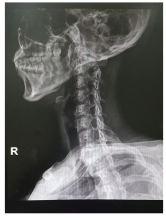

목디스크 증상 원인 치료방법 등 목 디스크 관련 정보에 대해 알아보도록 하겠습니다. 목 디스크는 목 뒤의 척추와 척추 사이에 있는 디스크라는 쿠션 역할을 하는 조직이 탈출하거나 파열되어 신경이나 척수를 압박하는 질환입니다.